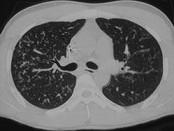

问题 男,26岁,发热,夜间盗汗,咳嗽半月余,请结合CT检查选出最可能的诊断 ( )

选项 A.粟粒型肺结核 B.间质性肺炎 C.弥漫型肺癌 D.肺转移瘤 E.硅沉着病

答案 A